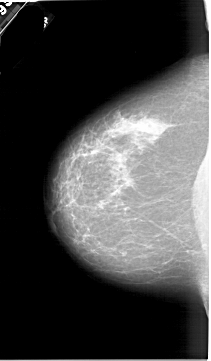

A_1767_1.RIGHT_MLO

LEFT_MLO LINES 5821 PIXELS_PER_LINE 3736 BITS_PER_PIXEL 12 RESOLUTION 43.5 NON_OVERLAY